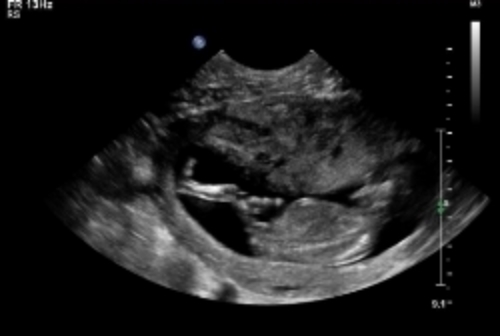

and a potty shot which i know isn't really accurate at this point

If the third pic has the nub (not an expert, so could be something else) I'd say boy!

she actually posted her own thread LOL. Possibly boy. Potty shot isnt viable at 13/6